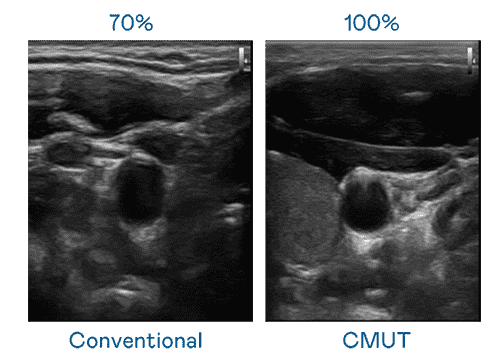

CMUT 技术是一种用电容式微机电元件来产生超音波讯号的技术。。与传统 PZT 压电式技术相比,,CMUT 频宽增加 30%,,更宽频的超音波讯号让影像解析度大幅提升,,是实现高影像品质医疗超音波扫描、、促进精准医疗发展的关键技术。。。

大频宽带来超清晰影像

超音波影像的解析度高低,,,,首先取决于探头能发出的讯号频宽。。。开云电子 CMUT 可提供高清晰的超音波讯号,,,,提供高频宽、、、、高灵敏度、、、、影像纹理细节更高的超音波影像,,,,协助医护人员缩短影像判读时间及利用精准的医疗影像进行诊断。。。。